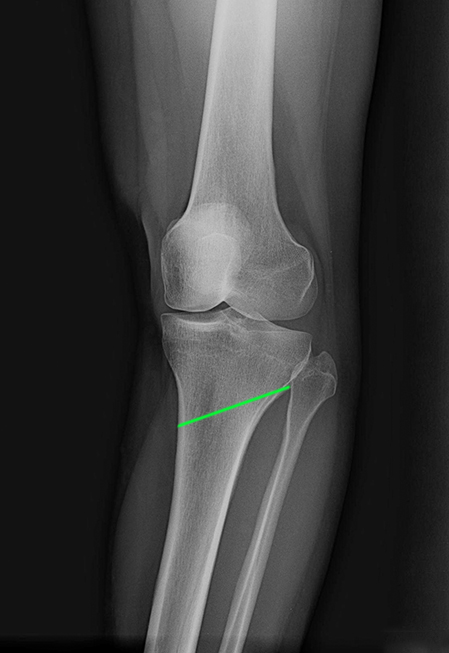

▲ 林女士左膝外側X光照

▲ 林女士左膝正面X光照,已接近膝蓋退化程度的第四期

最後別人介紹至□□醫院就醫,沒想到醫生看診不到1分鐘的時間就說要幫她安排最新的「高位脛骨截骨手術」,如此可使內側軟骨承重比例降低,能延後需要接受全人工關節置換手術的時間,以林女士的狀況來說,大概可以多撐個8年再來換人工關節。